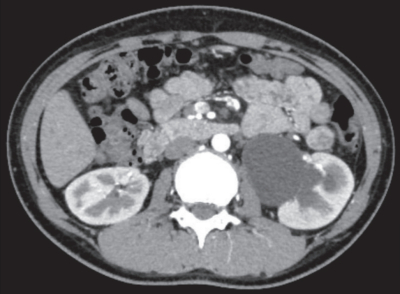

血液所見:赤血球 474 万、Hb 13.0 g/dL、Ht 40 %、白血球 6,500、血小板 28 万。血液生化学所見:総蛋白 6.7 g/dL、アルブミン 4.3 g/dL、総ビリルビン 0.3 mg/dL、AST 14 U/L、ALT 8 U/L、LD 156 U/L(基準 120~245)、尿素窒素 9 mg/dL、クレアチニン 0.5 mg/dL、尿酸3.5 mg/dL、 血 糖 82 mg/dL、Na 144 mEq/L、K 4.0 mEq/L、Cl 108 mEq/L、Ca 8.8 mg/dL。腹部単純 CT で尿路に石灰化陰影や走行異常を認めない。腹部造影 CT 水平断像、造影 CT 後の腹部エックス線写真及び利尿レノグラムを別に示す。